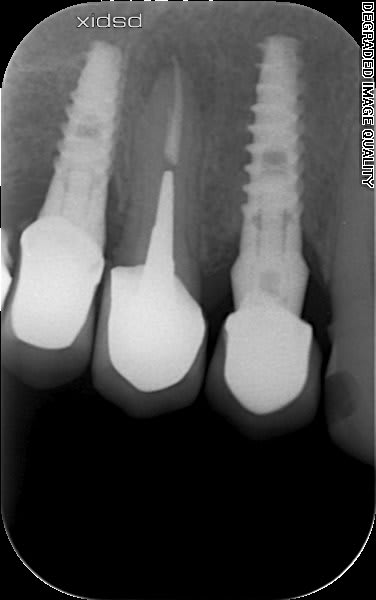

est ce que quelqu'un reconnait ces implants??